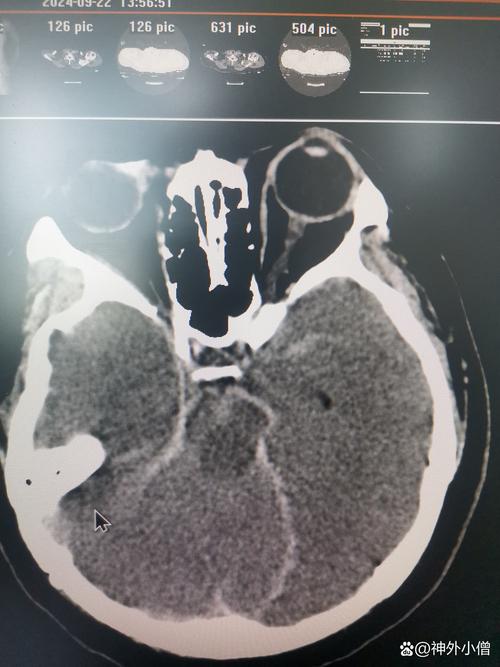

(图片来源网络,侵删)- 普通平扫CT:它主要是看密度变化,在发病超早期(6小时内),可能看不到明显异常,几小时到几天后,坏死的脑细胞会因为水肿而密度变低,这时才能看到低密度的梗死灶,但它无法区分哪些是已经坏死的“核心区”,哪些是濒临死亡的“半暗带”,它只能看到一个“模糊”的梗死整体。